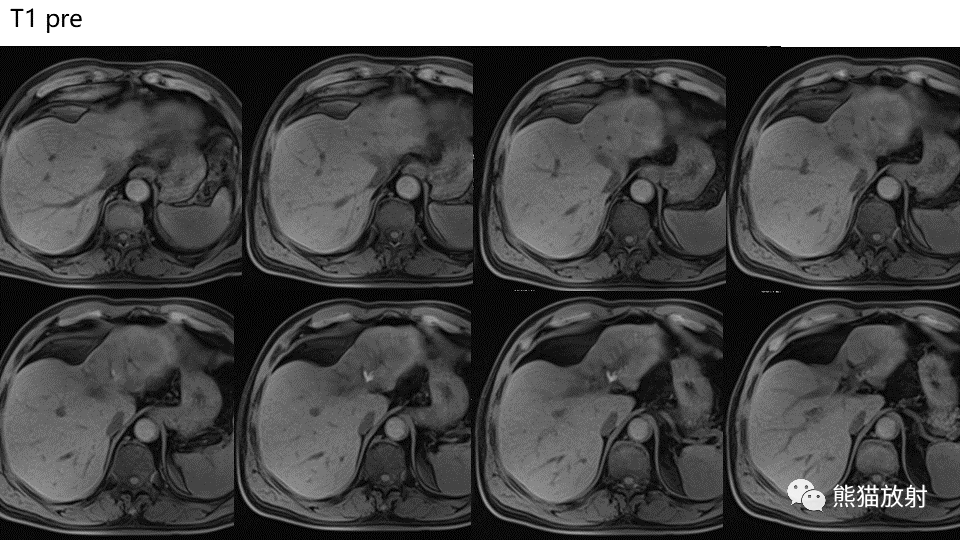

【PPT】肝内胆管细胞癌 VS 肝脓肿